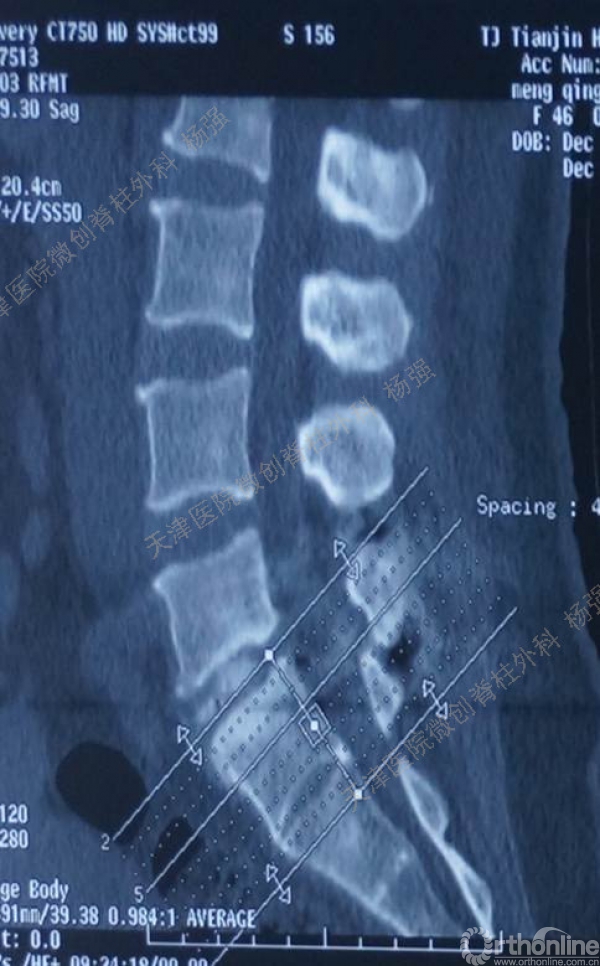

腰5椎体前滑脱I-II°,峡部裂,动力位显示腰5-骶1节段明显失稳

CT、MRI示:腰5椎体前滑脱,腰5/骶1水平间盘突出,腰5双侧椎弓峡部裂